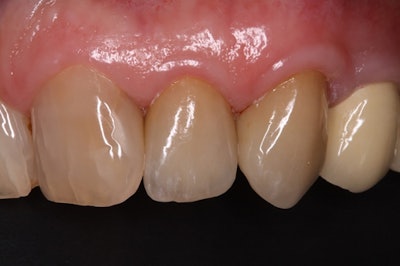

The patient's smile at a 55.8-month follow-up visit.

With a mean follow-up period of 36.5 months, all nine teeth were in situ with no clinical signs of inflammation and no biological complications in the surrounding periodontal tissues or the periapical regions. This resulted in a biological success rate of 100% up to 57 months following the procedure.